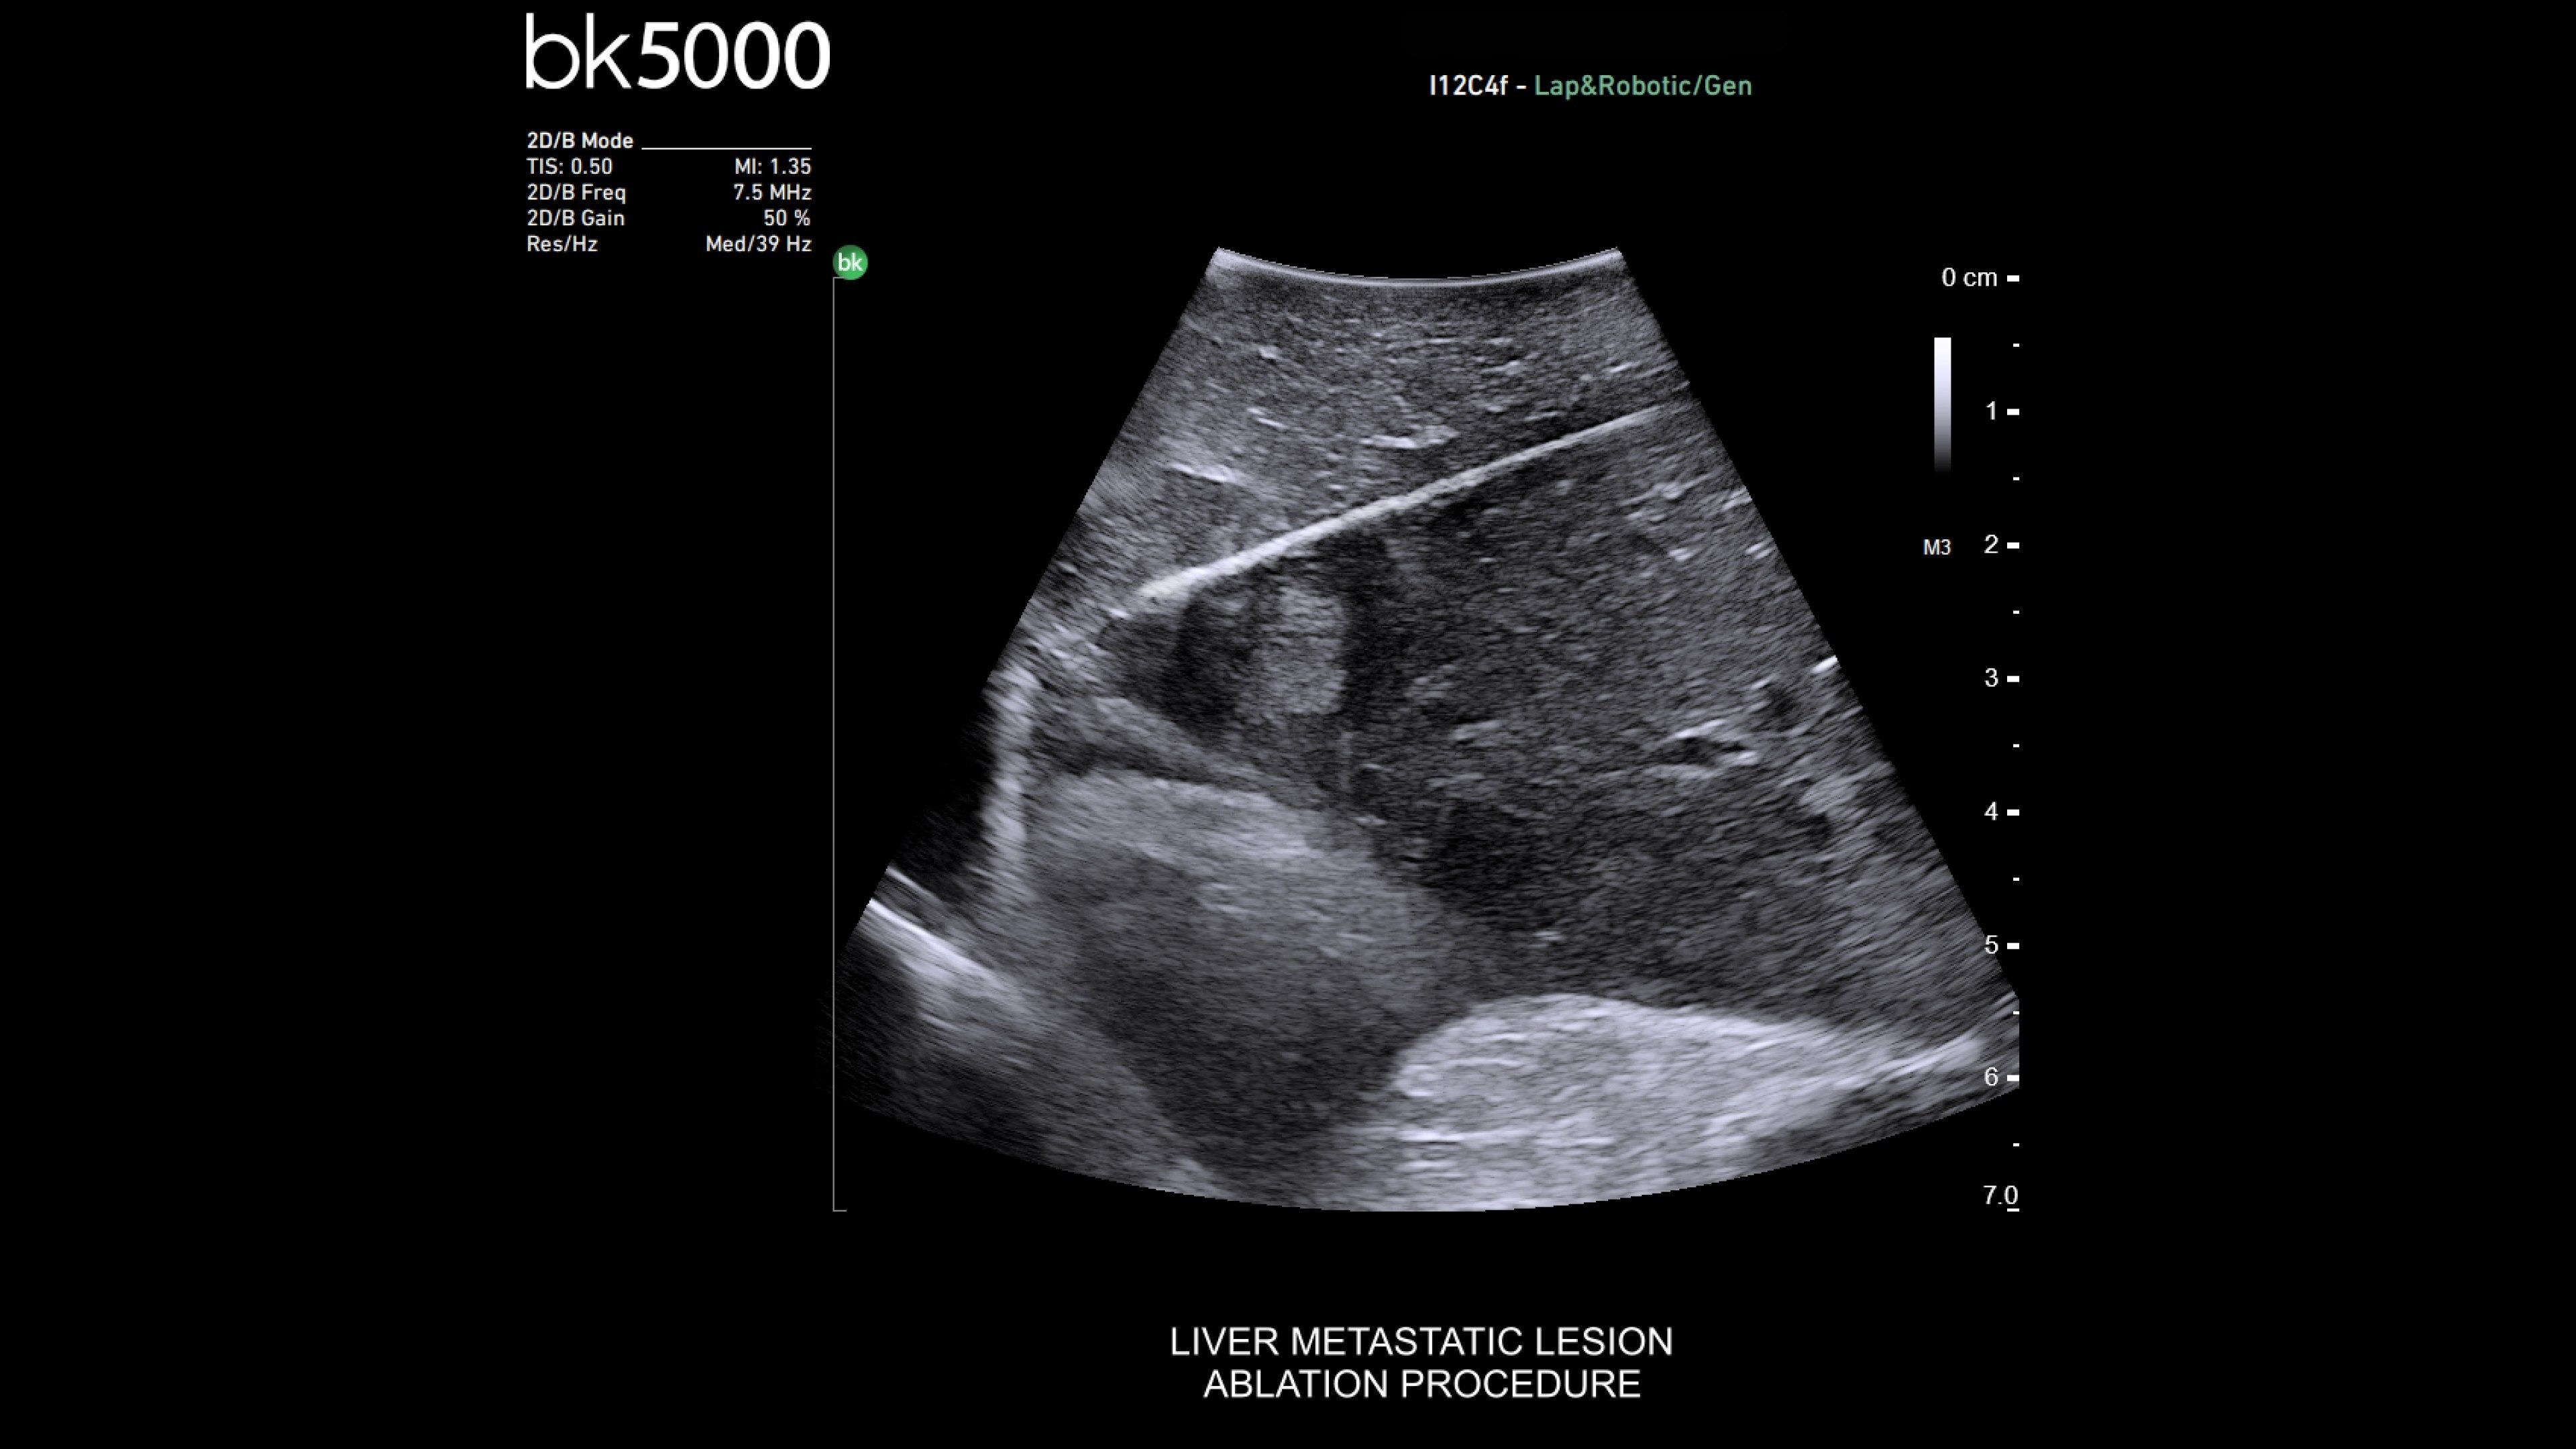

General surgery

Enhanced visualization for general surgery

The bkActiv ultrasound system delivers remarkable imaging for general surgery, including anorectal, robotics-assisted, and pelvic floor surgeries. Its advanced algorithms provide uniform image resolution and greater detail, while the remote control allows surgeons to adjust images within the sterile field. For anorectal surgeries, bkActiv offers high-definition imaging to visualize normal and abnormal anatomy, including anal sphincter injuries and rectal cancer. In robotics-assisted surgeries, the system's robotic transducers provide real-time, high-resolution imaging to locate and assess lesions and critical structures. For pelvic floor surgeries, bkActiv's advanced 3D architecture supports dynamic, real-time examination during procedures.